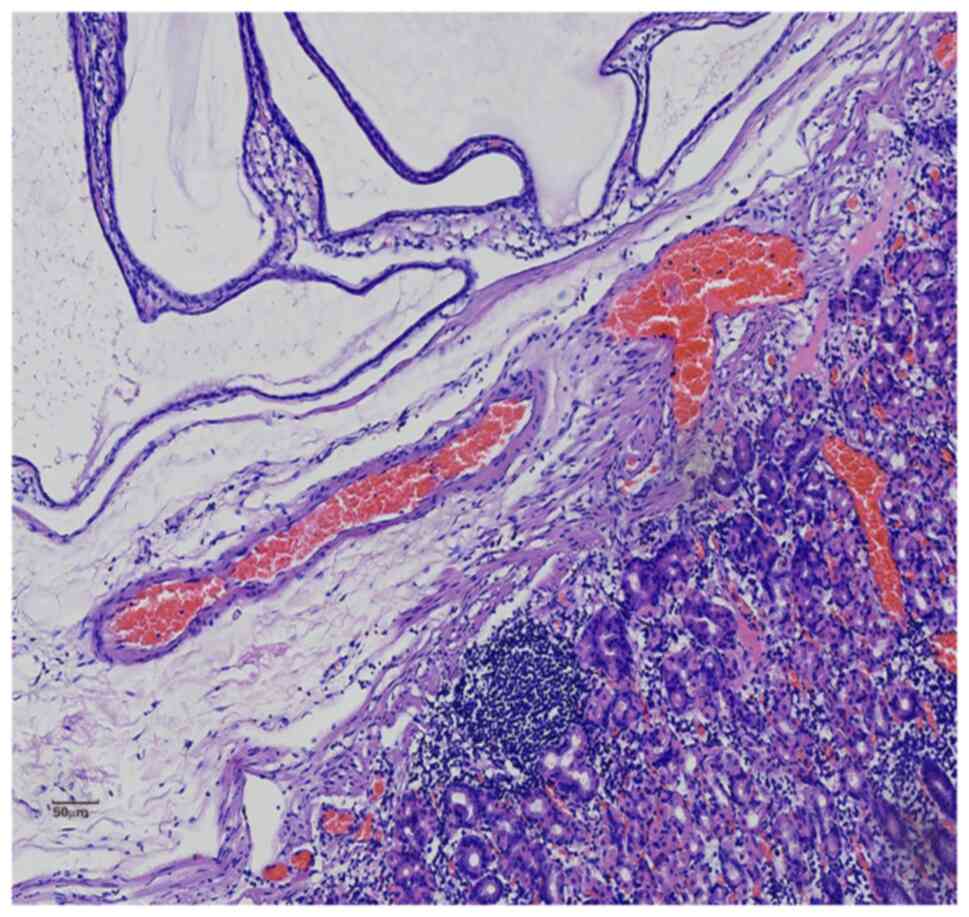

Gastric inverted hyperplastic polyp: A case report

Inverted hyperplastic polyp (IHP) is a rare disease characterized by the downward growth of proliferative mucosal components into the submucosal layer. It is often misdiagnosed as other submucosal tumors and accurate diagnosis requires pathological examination. Most patients with IHP have no clinical symptoms and some have non‑specific symptoms, such as abdominal distension, abdominal pain and even anemia. IHP is treated via endoscopic mucosal resection or endoscopic sub‑mucosal section. The present study reported a case of IHP and discussed its clinical manifestations, clinicopathological diagnosis, differential diagnosis and treatment to improve our understanding of the disease.

Figure 1

Figure 2

Figure 3

Figure 4

Figure 5

Figure 6

Figure 7